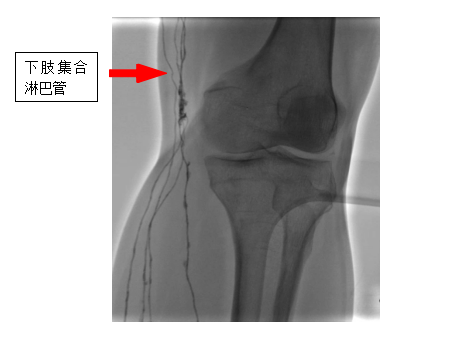

直接淋巴系統(tǒng)造影是一種先進(jìn)的醫(yī)學(xué)影像技術(shù)與手術(shù)的融合技術(shù),它通過超顯微技術(shù)將特殊的造影劑注入淋巴系統(tǒng),在數(shù)字減影設(shè)備下使淋巴管及淋巴結(jié)清晰顯影,從而能夠精確診斷淋巴系統(tǒng)的回流障礙、漏出、返流、畸形等疾病,對(duì)于淋巴管瘤、淋巴水腫、乳糜漏、淋巴結(jié)轉(zhuǎn)移癌等疾病的診斷和治療具有重要意義。